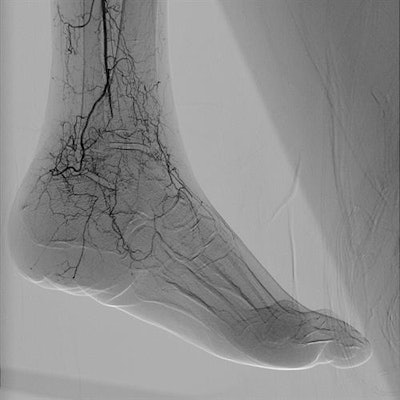

Alphenix is an interventional angiography platform that Canon Medical Systems is highlighting at the congress in Vienna. Enhancements include a conebeam CT mode called AlphaCT for low-contrast imaging and a real-time autopixel shift mode that cleans up imaging in less than 10 msec. The platform also includes the Hi-Def Detector, a flat-panel digital detector available on the Alphenix Biplane and Alphenix Core + systems.

An interventional suite that pairs an angiography system with a CT scanner -- called Alphenix 4D CT -- also is being demonstrated at the vendor's booth. The suite matches an Alphenix Sky + C-arm with an Aquilion One Genesis volumetric CT scanner, enabling clinicians to plan, verify, and treat patients in a single session.